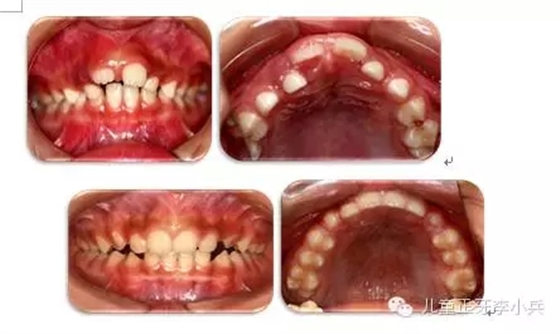

3. 牙槽骨早期塑形矯治:良好的咬合必須是上下頜骨大小位置正常、上下牙大小排列正常,以及上下牙弓的大小與形態(tài)協(xié)調(diào)。臨床功能矯形可調(diào)整上下頜骨大小與位置的不調(diào);臨床正畸治療可矯治牙齒排列異常。而上下牙槽骨的大小形態(tài)不協(xié)調(diào)的早期矯治就是牙槽骨的早期塑形。牙槽骨的發(fā)育包含牙槽骨長(zhǎng)、寬、高三項(xiàng)的發(fā)育,常見的牙槽骨發(fā)育異常是寬度的不足,形成功能性下頜后縮及牙列擁擠。早期的牙槽骨括弓能打開腭中縫,擴(kuò)大牙弓寬度,增加牙弓周徑,避免功能性II類及擁擠的發(fā)生。(圖4,早期牙槽骨塑形矯治)

圖4 上頜牙弓狹窄,牙槽骨擴(kuò)弓塑形促進(jìn)上下牙弓正常發(fā)育;